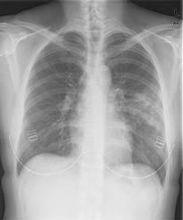

因小葉性肺炎多為其他疾病的併發症,其臨床症狀常為原發性疾病所掩蓋。由於支氣管黏膜的炎症刺激而引起咳嗽,痰呈粘液膿性。因病變常呈灶性散布,肺實變體徵一般不明顯。病變區細支管和肺泡內含有滲出物,聽診可聞濕囉音。X線檢查,可見肺野內散在不規則小片狀或斑點狀模糊陰影。本病發現及時,治療得當,肺內滲出物可完全吸收而痊癒。但在幼兒,年老體弱者,特別是並發於其他嚴重疾病時,預後大多不良。